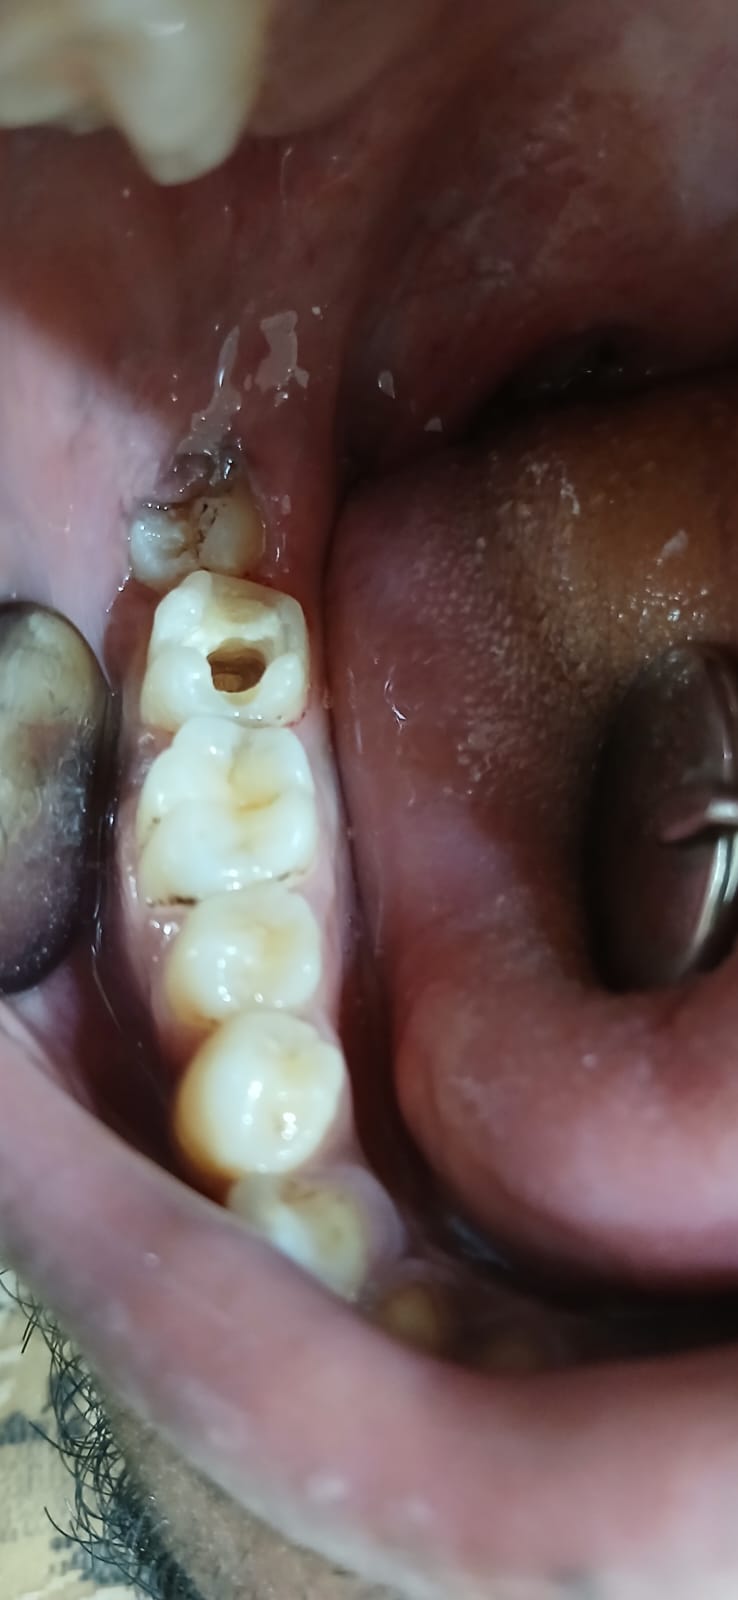

আগে ও পরে

আমাদের সফল কম্পোজিট রেস্টোরেশনের কিছু উদাহরণ

সামনের দাঁতের ক্ষয় মেরামত

ভাঙা দাঁত পুনর্গঠন

দাঁতের ফাঁক বন্ধ

ছবিতে ক্লিক করে বড় করে দেখুন। আরও কেস স্টাডি দেখতে ক্লিনিকে আসুন।